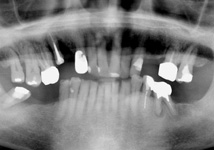

長年放置したために歯周病が進行し、尚且つ入れ歯が噛みにくくなったと受診され、両サイドの奥にインプラントを入れ全顎的な治療を行い審美改善しました。

今は見た目もよくなり、よく噛めるようになったと喜んでいらっしゃいます。 |